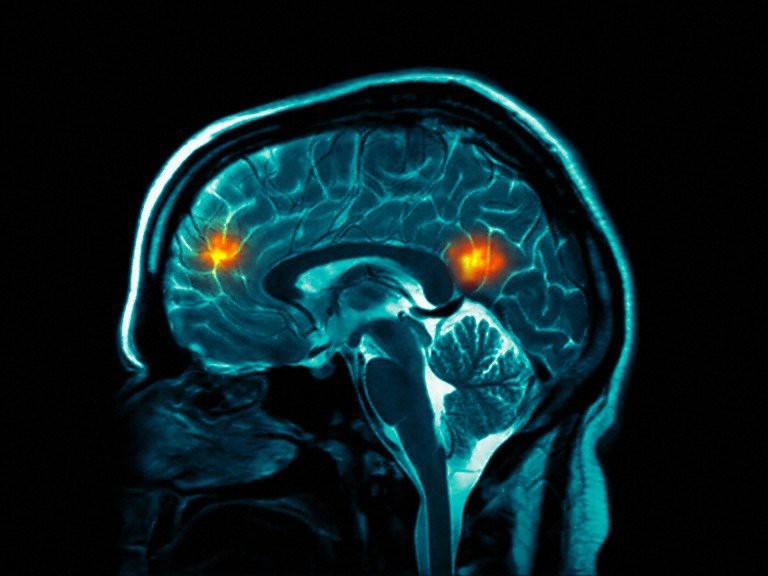

محققان با استفاده از امآرآی به اسکن مغز 885 انسان از سه تا 20 سال پرداختند. این اسکنهای مغزی برای شناسایی 231 نشانگر زیستی آناتومی مغز مورد استفاده قرار گرفتند که در زمان ترکیب شدن میتواند سن فرد را با دقت تا 92 درصد نشان دهند.

به گفته محققان این عملکرد ماورای سنجشهای دیگر بیولوژیکی است. در حالیکه سنجشهای دیگر در گذشته از تک تک نشانگرهای زیستی مشابه استفاده میکردند، کلید این معما، شناسایی راهی برای ترکیب این نشانگرها برای ثبت طبیعت چند بعدی آناتومی مغز و الگوهای خاص تغییر رشد با بالا رفتن سن بود.

به گفته دانشمندان، این حقیقت که آنها موفق به کشف مجموعهای از سنجشهای مغزی شدهاند که بطور دقیق میتواند سن تقویمی فرد را تشخیص دهد، بدین معنی است که رشد مغزی یا حداقل جنبههای آناتومیک آن بسیار بیشتر آنچه تاکنون تصور میشدف تحت کنترل است.